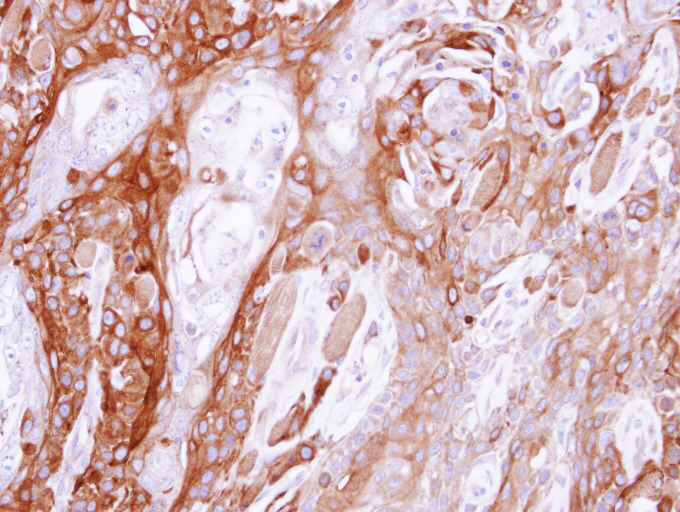

Supportive validation

- Submitted by

- Signalway Antibody LLC (provider)

- Main image

- Experimental details

- Immunohistochemical analysis of paraffin-embedded CA922 xenograft, using UBE4B antibody at 1: 500 dilution.